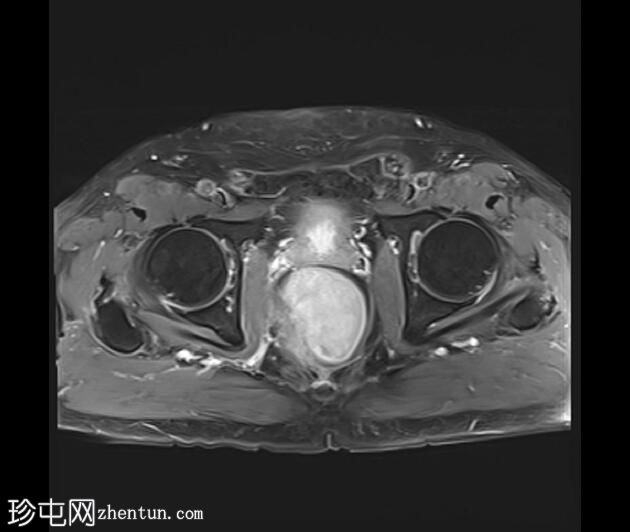

MRI

轴位

8.jpeg

T1加权像

可见一不规则分叶状肿块,累及直肠中段和远端,头尾方向长约7 cm,下缘距肛缘约2.5 cm。在T1加权像和T2加权像上,该病灶相对于骨骼肌均呈高信号。 PDFS(脂肪抑制)图像显示持续高信号强度,提示存在黑色素和/或出血成分。

增强扫描显示病灶内呈不均匀强化。直肠下段7点钟位置的系膜筋膜受累。后方系膜可见少量淋巴结。未见邻近器官侵犯。